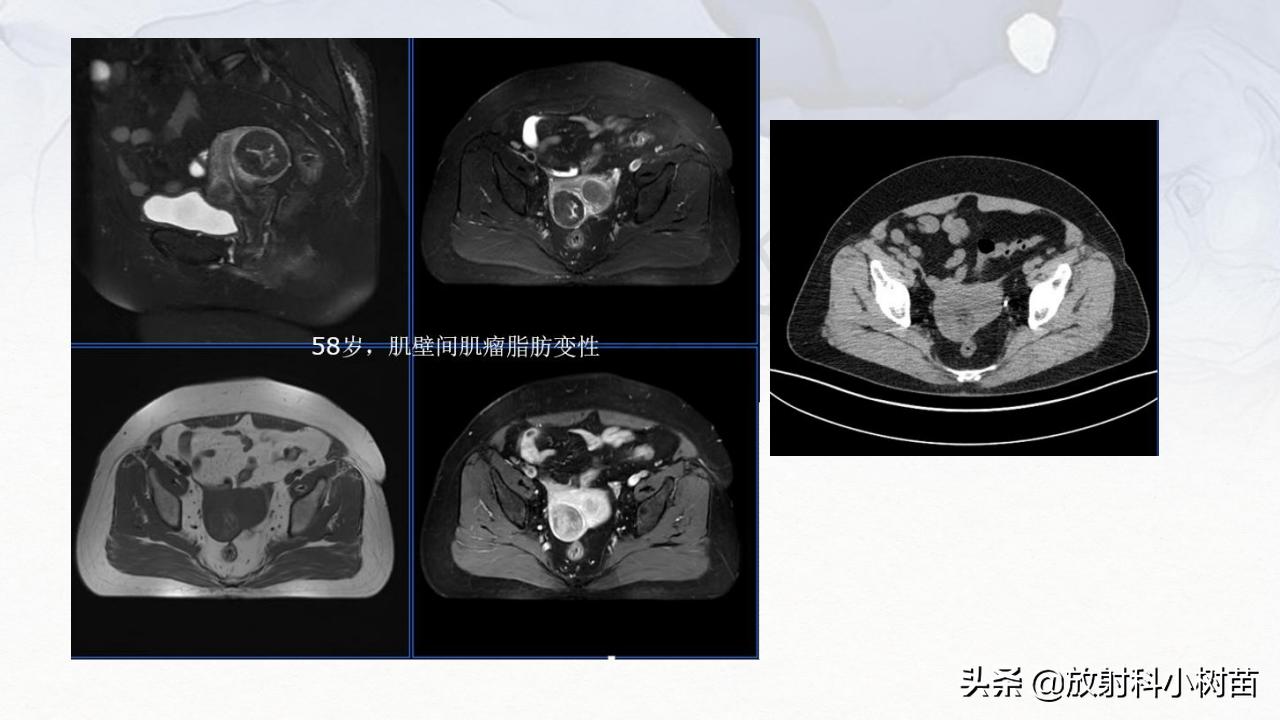

子宫体:肌层?(腺肌症,肌瘤,肉瘤),内膜?(增生,息肉、内膜癌)